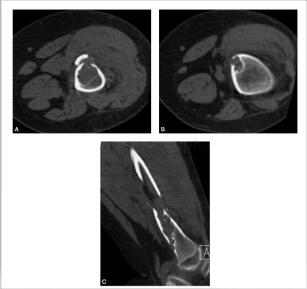

半个月前无明显诱因患儿自述走路时左侧膝部疼痛,左膝关节活动无明显影响。病来无发热、无盗汗。查体:患儿左胫骨近端无明显肿胀,无红肿,表面无破溃,无静脉怒张,局部无压痛,膝关节伸屈活动不受限(图3~5)。

图3 X线:左侧胫骨近侧干骺端可见多发囊状低密度影,周围可见硬化缘,邻近骨皮质略膨胀,周围软组织未见肿胀

图4 CT:左胫骨近端髓腔内及皮质内多发囊状骨质密度减低区,边缘见硬化缘,部分囊变区内见小结节状高密度影,左胫骨近端局部骨皮质缺损

图5 MR:左胫骨近段见多发长椭圆形短T1短T2信号影,部分信号增高,周围见低信号影环绕